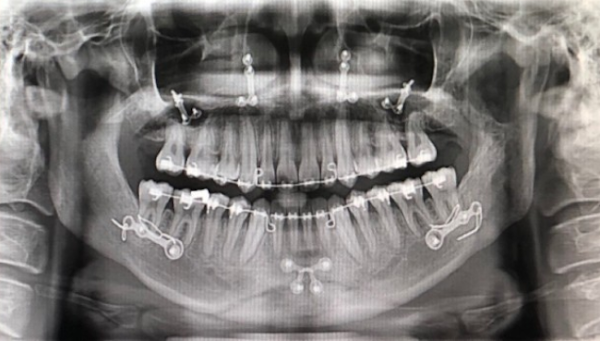

악(顎)교정술(턱의 위치나 모양을 변형시키는 수술)의 일종으로 윗턱인 상악(上顎)과 아랫턱인 하악(下顎)을 함께 수술하는 경우 양악(兩顎)수술이라 칭한다. 쉽게 말해 코 밑부터 아래턱 뼈 부분을 잘라내서 턱을 축소시켜, 얼굴을 바꾸는 치과 영역의 대수술.

양악수술을 하는 방법은 상악과 하악의 뼈를 잘라서 2개로 분리한 다음 정상 교합에 맞게 상악과 하악의 뼈를 이동시키고 이동된 뼈를 고정하는 방법이다. 뼈를 이동하는 대수술인 만큼 수술은 전신마취로 진행되며 보통 3일~7일 정도 입원하게 된다.

양악수술 한 사람의 엑스레이 상태